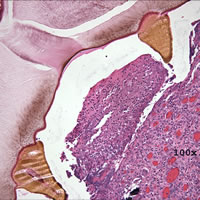

Case

98:

A 5-year-old girl developed an earache after vacationing in Belize with

her parents. A few months after returning from the vacation, her

parents took her to a New York City hospital for the earache where a biopsy

specimen was taken from her left ear. Her parents reported that

she had gone swimming during the trip. The following images

are from H & E (hematoxylin and eosin) stained sections of the biopsy. What

is your diagnosis? Based on what criteria?